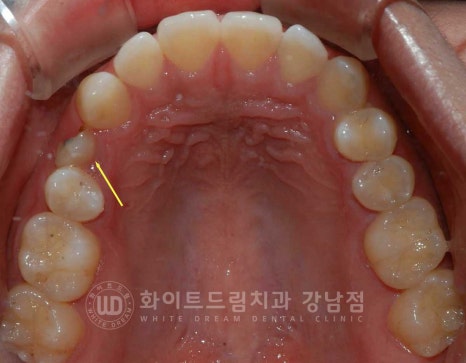

환자분은 23.08.04 식립 후 4개월 뒤 임플란트 보철 세팅을 진행했고

총 5개월의 치료 기간으로 모든 치료가 마무리되었답니다.

치료 기간 23.08.04 - 24.01.05

동일 인물이며 동일 환경에서 촬영됨

▲ 스케일링 후 촬영하여 사진에 출혈이 조금 보이는데 참고해 주시기 바랍니다. ^^